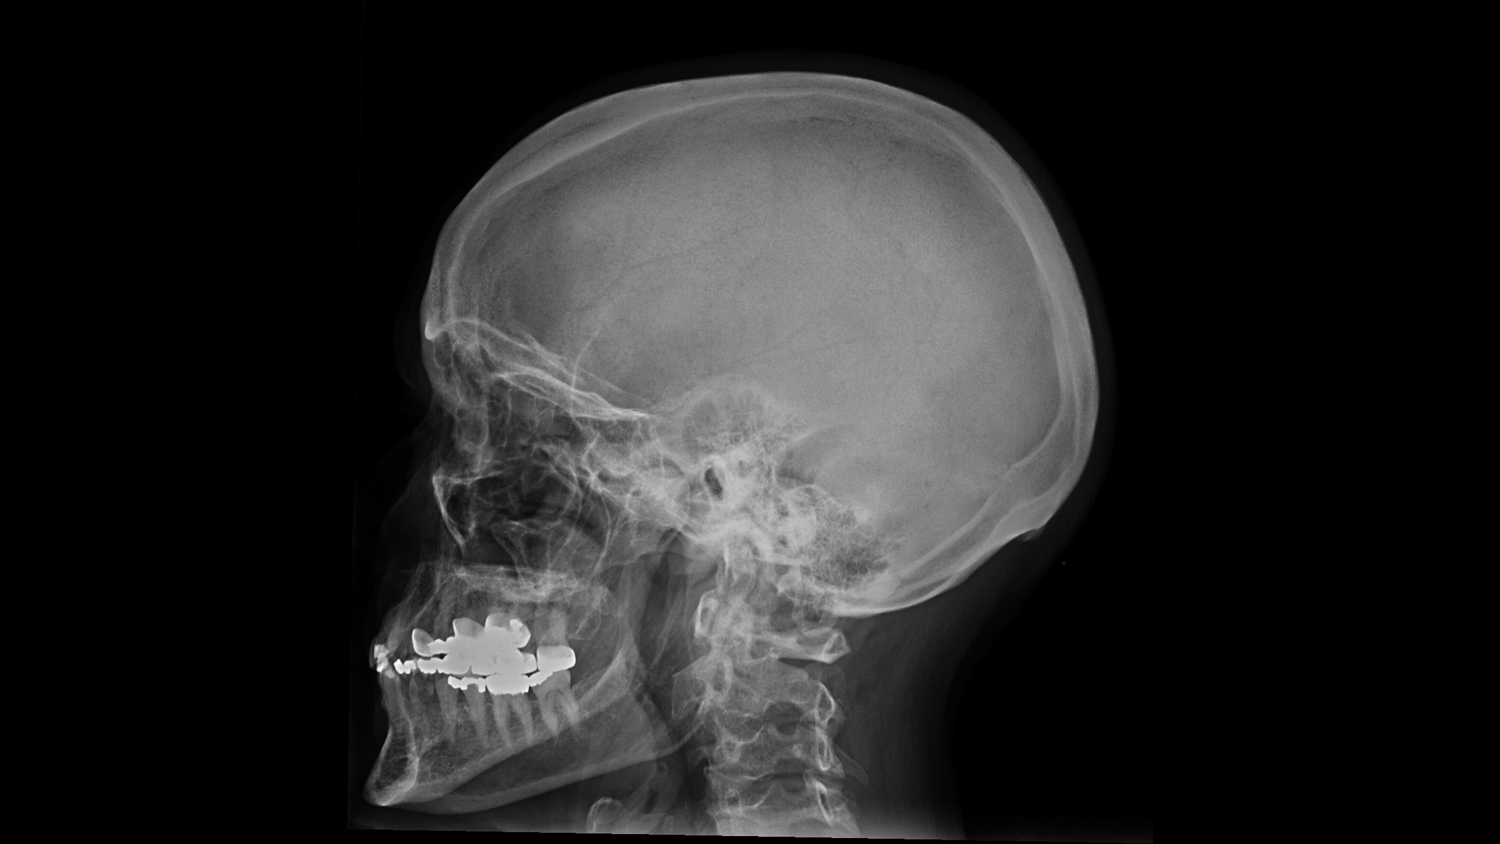

Рентгенография черепа и позвоночника: изображение и диагностика